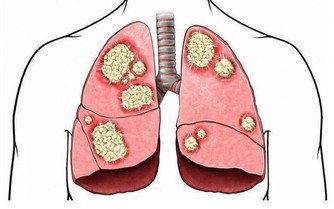

癌症是人人聞之色變的一種疾病,有很多種癌症至今都沒有治癒的方法。癌症也被稱為「絕症」,只要聽說某個人罹患癌症,基本就是下了死亡判決書。癌症有一個特點大家必須要知道,就是35℃下是癌細胞最喜歡的溫度,也是令它們最活躍的溫度。 一旦身體溫度高於39.6℃,癌細胞就會死亡! ▼過去患癌症的人遠不如現在多,大部分現代人由於壓力過大和飲食不當等原因,正常體溫都在35℃-36℃,而這種「低體溫狀態」正是高血壓、高脂血症、糖尿病、肥胖、更年期障礙、憂鬱症、心肌梗塞、癌症等疑難雜症高發的重要原因。總而言之,體溫是決定生老病死的關鍵。